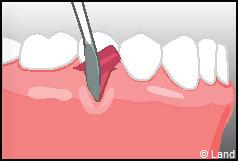

Les greffes de conjonctifs enfouis :

Destinées aux zones esthétiques, elles consistent à prélever la partie profonde du palais (site donneur).

Ce greffon est ensuite inséré sous la gencive au niveau de la récession (site receveur).